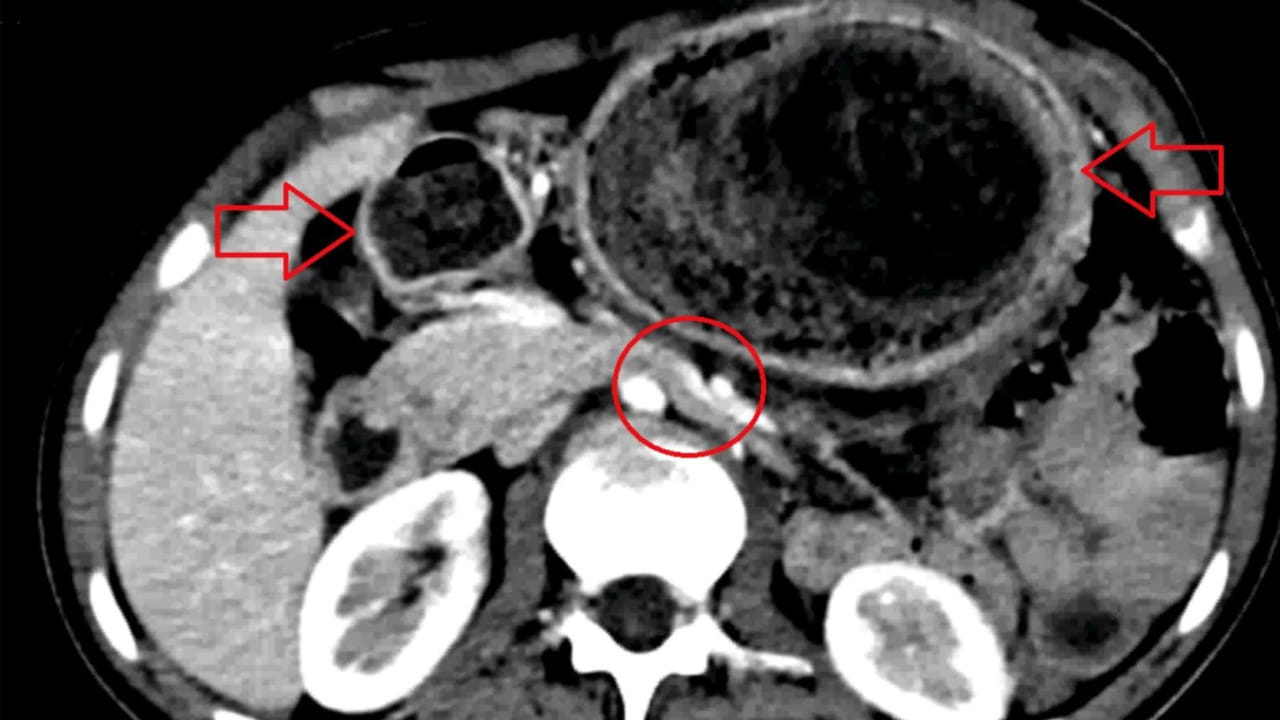

ఓ టీనేజర్ కడుపు నుంచి 4 పౌండ్ల బరువున్న భారీ వెంట్రుకల ముద్దను తొలగించారు డాక్టర్లు. ఆమె చిన్ననాటి నుంచి ట్రైకోటిల్లోమానియా అనే వ్యాధితో బాధపడుతోందని చెప్పారు. ఈ జబ్బు ఉన్నవారు జుట్టును తరచూ నమలడం, తినడం లాంటివి చేస్తారని చెప్పారు. దీని ఫలితంగానే ఆమె కడుపులో వెంట్రుకల ముద్ద ఏర్పడిందని తెలిపారు. CT-స్కాన్లో డాక్టర్లు ఈ హెయిర్బాల్ గుర్తించేసరికి.. సదరు యువతికి మానసిక చికిత్స పూర్తయిందట. ఈ వ్యాధి కారణంగా ఆమెకు తరచూ బరువు తగ్గడం, తీవ్రమైన కడుపు నొప్పి లాంటి లక్షణాలు వచ్చాయట.

గడిచిన ఆరు వారాల నుంచి తీవ్రమైన పొత్తికడుపు నొప్పితో ఆ 19 ఏళ్ల యువతి ఆస్పత్రిలో జాయిన్ అయింది. నొప్పి ఒక వారం పాటు కొనసాగగా.. రెండు నెలల పాటు ఆహారం తీసుకున్న వెంటనే పదేపదే వాంతులు రావడంతో పాటు, తేలికపాటి అనోరెక్సియా కూడా వచ్చేదట. అల్ట్రాసౌండ్, CT స్కాన్లో ఆ హెయిర్ బాల్ పరిమాణం డాక్టర్లకు స్పష్టంగా తేలింది. సుమారు రెండు గంటల పాటు శస్త్రచికిత్స నిర్వహించి కడుపులో 10 సెం.మీ, 4 పౌండ్ల హెయిర్ బాల్ తొలగించారు. ఈ ఆపరేషన్ అనంతరం.. యువతి పలు ఫ్లూయిడ్స్ ఎక్కించి.. ఆ తర్వాత డిశ్చార్జ్ చేశారు. కాగా, మూడు నెలల పాటు ఫాలో-అప్ తర్వాత సదరు యువతి పూర్తిగా కోలుకుంది.